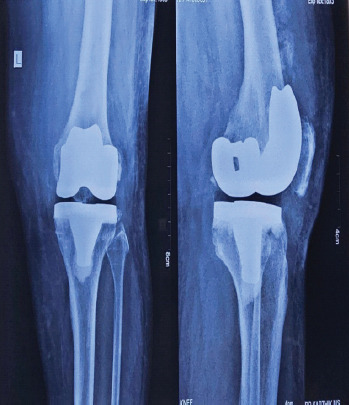

Case report: We report the case of a 67-year-old female with grade 4 osteoarthritis of the left knee who underwent TKR following the failure of conservative management. Postoperatively, the patient developed stiffness and a reduced range of motion. Radiographic imaging at 5 weeks showed haziness in the anterior aspect of the femur at the upper border of the femoral implant, with gradual progression to distinct ossification by 3 months.

Results: The heterotopic bone formation was found to impinge on the quadriceps mechanism, limiting knee flexion but not preventing full extension. Conservative management involving physiotherapy and analgesics was pursued, and surgical excision was avoided initially. Over 1 year, the patient showed improvement in extension, although no significant improvement in flexion was observed. Surgical excision of the heterotopic bone was performed at the end of 1 year, followed by post-operative radiotherapy to prevent recurrence.